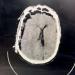

إنقاذ حياة مريض سبعيني من نزيف حاد بالمخ بمستشفى ميت غمر بالدقهلية